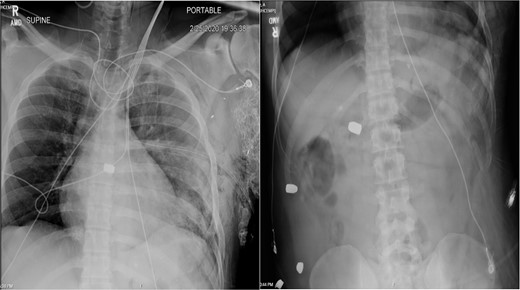

A 36-year-old male presented with multiple thoracoabdominal GSW (4 GSW in the left axilla, 2 GSW right flank). The patient had decreased breath sounds on the left. Initial vital signs were heart rate 141, blood pressure 70/40, respiratory rate 22, saturation 92% on 15 L non-rebreather, GCS 14. The patient underwent a left thoracostomy tube with 1000 mL initial output and a 9F left femoral central line was placed. The patient was initially resuscitated with 2 units PRBC, 2 units FFP with no improvement in vital signs. A plain film X-ray in the trauma bay revealed multiple thoracoabdominal bullets (Fig. 3). The patient went emergently to the OR for hemorrhage control.

Plain film X-ray obtained in the trauma bay demonstrating multiple bullets overlying the cardiac silhouette and right abdomen.